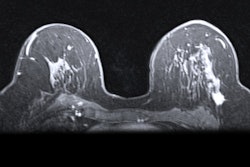

MBI uses a small-field-of-view gamma camera to image radiotracer uptake within the breast, and it is used as a supplement to screening with standard digital mammography or to guide treatment. Previous research suggests that MBI has a supplemental cancer detection rate of eight to nine cancers per 1,000 women screened when used along with digital mammography.

Breast radiologists developed a lexicon in 2012 for MBI that mirrors the lexicon used for imaging descriptors in the BI-RADS atlas. This lexicon includes descriptors for mass versus nonmass radiotracer uptake, distribution of nonmass uptake, and lesion intensity.